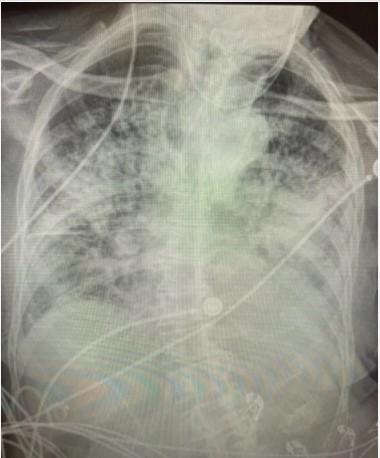

Рентгенівський знімок курця був нечітким, в той час, як рентгенівський знімок пацієнта з COVID виглядав майже повністю білим. Помутніння легенів зазвичай вказує на те, що вони наповнені такими речовинами, як рідина або бактерії, а також щільними рубцями і ушкодженнями, пояснила лікар.

Лікар додала, що коронавірус часто призводить до таких ускладнень, як пневмонія, яка виникає, коли в легені надходить рідина і вони запалюються. Оскільки повітряні мішечки наповнюються речовиною, вони не можуть приймати достатньо кисню, що призводить до таких симптомів, як кашель і задишка.

«Все ще є люди, які кажуть: «Я в порядку, у мене немає проблем», але коли вони роблять рентген грудної клітини, видно, що він абсолютно поганий», – підсумувала вона.Легені пацієнта після COVID-19